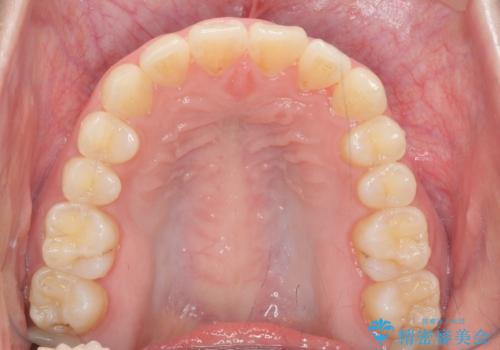

- ねじれの目立つ前歯の見た目を改善したいと矯正治療を希望され来院されました。

がたつきの改善をマウスピース矯正インビザラインで行っていきます。

ガタつきの改善はもちろん、歯列全体のアーチも放物線状にきれいに排列し審美性を向上させることができました。